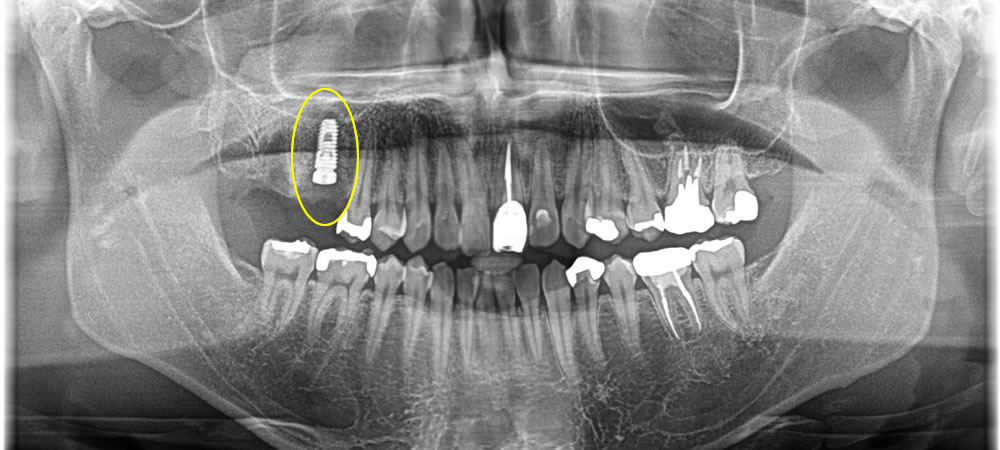

パノラマレントゲン写真にてチェックをしたところ、歯の根っこが割れて残っており、周りの骨も無くなってしまっている事が確認できました。治療方法を話し合った結果、残っている根を抜き手前の1本をインプラントでの治療をご希望されました。

インプラント治療完了後のレントゲン・口腔内写真

その後、2週間で抜糸をし、4ヶ月置きしっかりとインプラント体が骨とオステオインテグレーションしているのを確認し、上部に歯を作成しました。

今回は、スクリューで上部の歯を止める形で完了しました。結果、自然な歯になり、1本にはなりますが、奥歯での咬合の回復を行う事ができました。